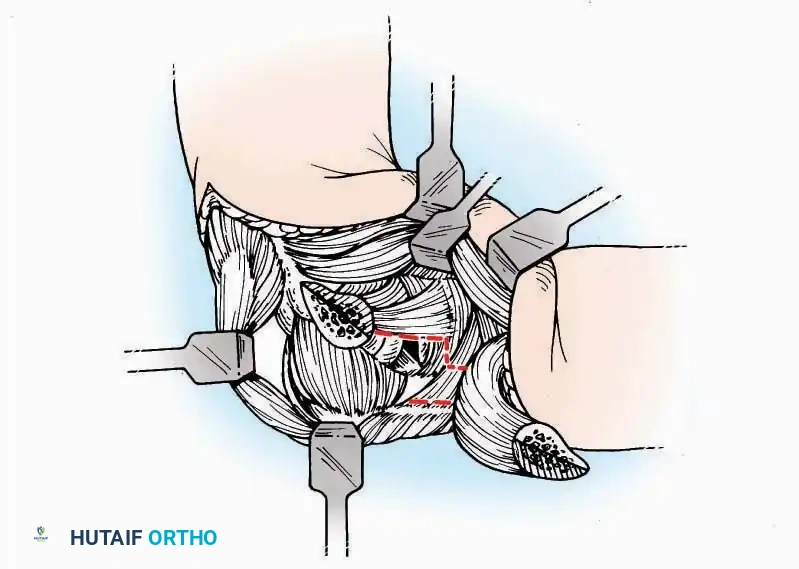

SURGICAL APPROACHES TO THE TARSUS AND ANKLE

Anterolateral Approach

The anterolateral approach is widely considered the "universal incision" for the foot and ankle. It provides unparalleled access to the ankle joint, the talus, and the majority of the tarsal articulations, while safely avoiding the major anterior neurovascular bundle. The only tarsal joints inaccessible via this route are the naviculocuneiform joints (specifically the medial and intermediate).

Indications: Total talectomy, triple arthrodesis, ankle arthrodesis, and open reduction of complex talar neck fractures.

Surgical Technique:

* Incision: Begin over the anterolateral aspect of the leg, medial to the fibula and 5 cm proximal to the ankle joint line. Carry it distally over the joint, crossing the anterolateral aspect of the talar body and the calcaneocuboid joint, terminating at the base of the fourth metatarsal.

* Superficial Dissection: Incise the superficial fascia and the superior and inferior extensor retinacula down to the periosteum of the tibia and the ankle joint capsule.

* Vascular Ligation: This trajectory usually requires the identification and ligation of the anterolateral malleolar and lateral tarsal arteries.

* Nerve Protection: Retract the skin edges carefully. Identify and protect the intermediate dorsal cutaneous branches of the superficial peroneal nerve (SPN), which frequently cross the distal aspect of this incision.

* Muscle Management: Identify the origin of the extensor digitorum brevis (EDB) muscle on the lateral calcaneus. Divide it in the direction of its fibers, or detach its origin entirely and reflect it distally to expose the subtalar and calcaneocuboid joints.

* Deep Exposure: Retract the extensor digitorum longus (EDL) tendons, the dorsalis pedis artery, and the deep peroneal nerve (DPN) medially. Incise the anterior ankle capsule to expose the tibiotalar joint.

* Tarsal Exposure: Expose the talonavicular joint by dissecting deep to the extensor tendons and incising its capsule transversely. Continue laterally through the capsule of the calcaneocuboid joint. By excising the fat pad within the sinus tarsi (lateral and inferior to the talar neck), the posterior facet of the subtalar joint is brought into direct view.